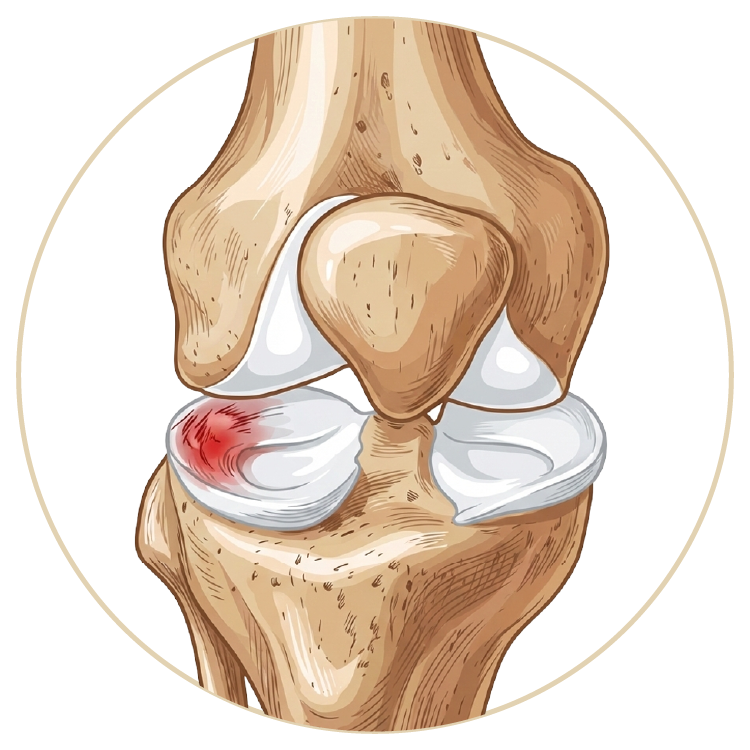

Menisküs Yırtığı

Menisküs Nakli

Kıkırdak Yaralanmaları